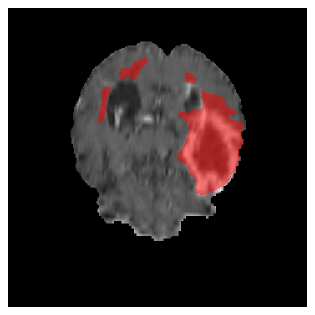

Appendix A Qualitative results

Figure 5 illustrates the segmentation evolution for the same BRATS patient in S2 sequence. The key difference here is that the best buffer-free strategy is EWC (=1), and training on BRATS data starts from episode 2 instead of episode 1 as BRATS is encountered at episode 2 in S2. The cumulative approach retains segmentation across episodes but continues to generate false positives, which become even more pronounced in the final episode. The naive approach, lacking a CL mechanisms, completely overrides previous knowledge, leading to failed segmentation in later episodes. EWC (=1) approach initially maintains segmentation but experiences a sharp decline in episode 4, where it fails to segment the tumor. In the final episode, it undersegments the lesion, missing a significant portion of the tumor. In contrast, the proposed approach consistently preserves segmentation across episodes. While initially introducing false positives, it gradually refines predictions, retaining the tumor region while minimizing misclassifications. It maintains clear tumor delineation by the final episode, demonstrating effective knowledge retention and adaptability throughout training.